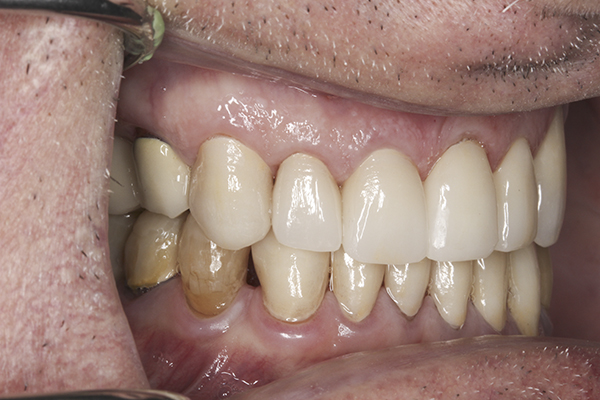

(35.) Postoperative right lateral, closed view.

Figure 35

(36.) Postoperative anterior, closed view. Note the position of the upper and lower canines to provide canine guidance.

Figure 36

(37.) Postoperative left lateral, closed view.

Figure 37